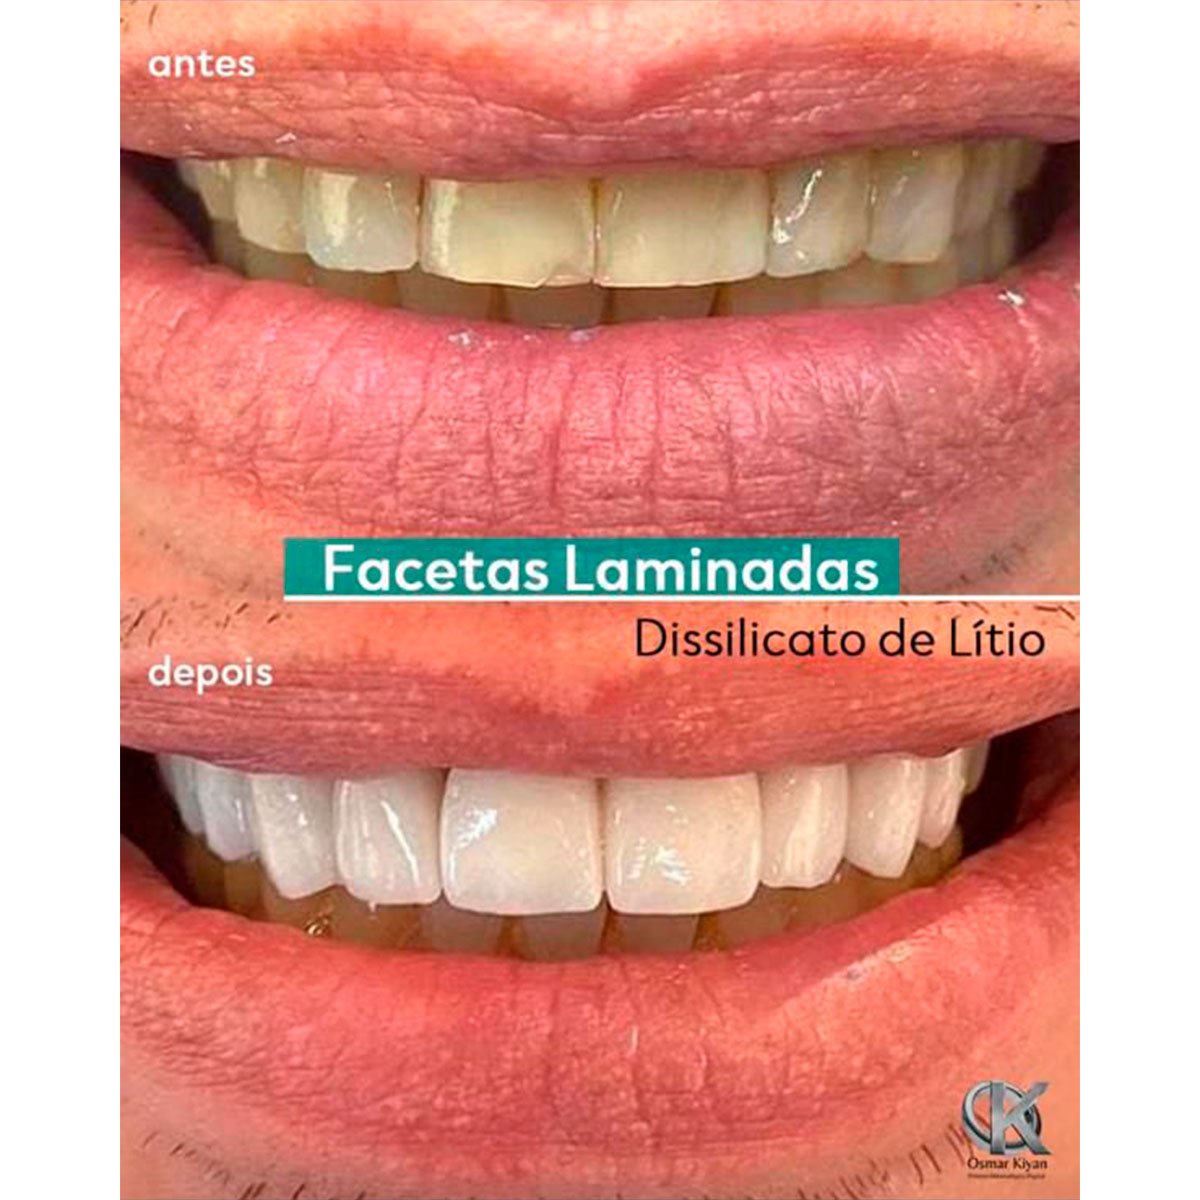

Tecnologia e precisão para o seu sorriso

Para aproveitar o melhor da nova Odontologia, é fundamental trabalhar em equipe. Esse é o espírito do Kiyan, que conta com uma equipe altamente capacitada e especializada, liderada pelo técnico Osmar Kiyan.

Para que o seu trabalho seja um sucesso, atuamos com dois times integrados. O primeiro é formado pela equipe do laboratório, sempre alinhada para realizar o melhor trabalho laboratorial. O segundo — e mais importante — é composto por você e pelo nosso laboratório.

Esse é o verdadeiro time vencedor, pois une o melhor da Odontologia clínica e laboratorial, trabalhando pelo mesmo ideal.

O Kiyan trabalha com o máximo empenho para oferecer a mais alta qualidade em serviços e tecnologia. Para tal, o Laboratório busca, sempre em conjunto com as mais destacadas empresas do segmento, oferecer a você as ferramentas e soluções mais adequadas às suas necessidades no atendimento do seu paciente.